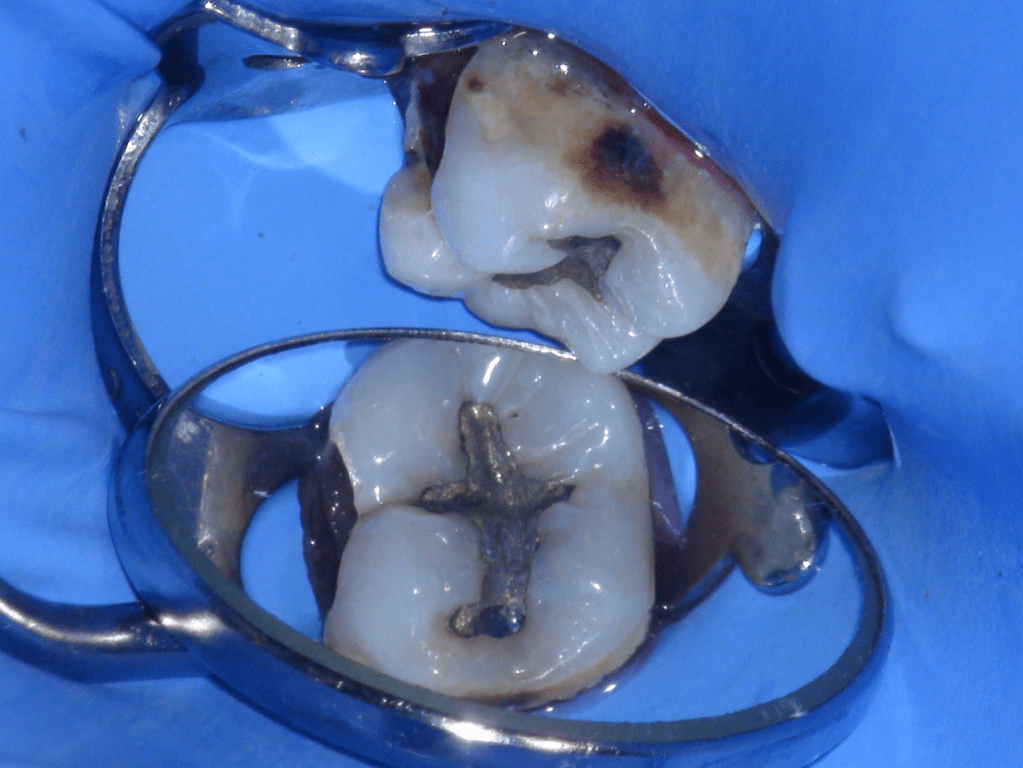

Fisura, remoción amalgama para explorar